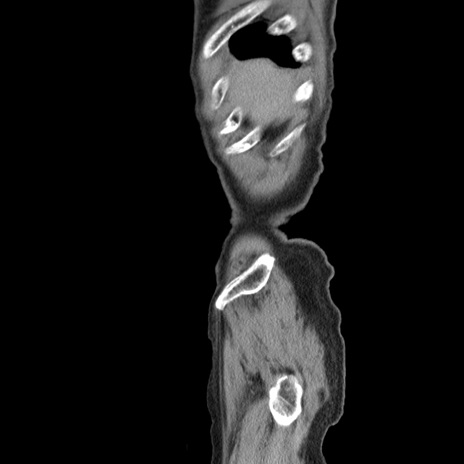

症例24(矢状断像)

横断像